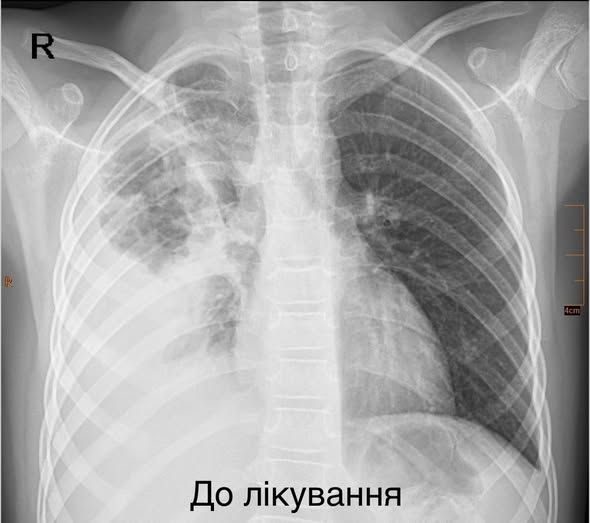

Легені дитини на момент госпіталізації

Усе почалося як звичайна застуда, а невдовзі стан дитини різко погіршився. До Центру (лікарню «Охматдит») дівчинку привезла «швидка» у важкому стані: з високою температурою, задишкою, низькою сатурацією кисню у крові. Її відразу госпіталізували у Клініку торакальної хірургії, де розпочали інтенсивну терапію: призначили потужні антибіотики, щоб зупинити інфекцію, інфузійну та кисневу терапію. Та без операції у цій ситуації обійтися було неможливо: хірургам треба було забрати з легені гнійно-некротичні вогнища, що утворилися, і врятувати дитині легеню, повідомили у медзакладі.